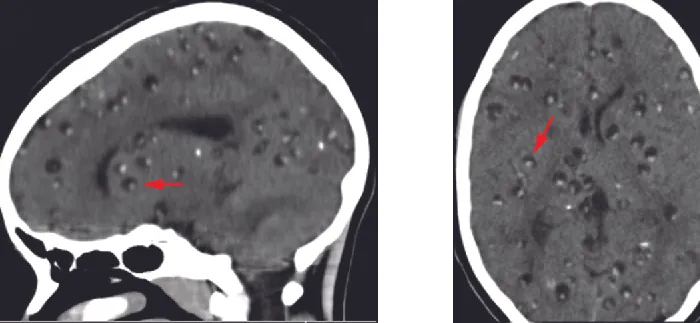

Neurocysticercosis is usually diagnosed through noninvasive techniques. Epidemiological information can be used as an initial screen; cysticercosis is endemic in Central and South America, Africa, and Asia. Radiological imaging (MRI and CT scans) is the primary method used to diagnose neurocysticercosis; imaging can be used to detect the one- to two-centimeter cysts that form around the parasites (Figure 26.26). Elevated levels of eosinophils in the blood can also indicate a parasitic infection. EIA and ELISA are also used to detect antigens associated with the pathogen.

Brain scans with small lumps (look like pimples) indicated by arrows.

Figure 26.26 Brain CT scans of sagittal (left) and axial (right) sections of a brain with neurocysticercosis. Numerous cysts are visible in both images, as indicated by the arrows. (credit: modification of work by Segamwenge IL, Kioko NP)